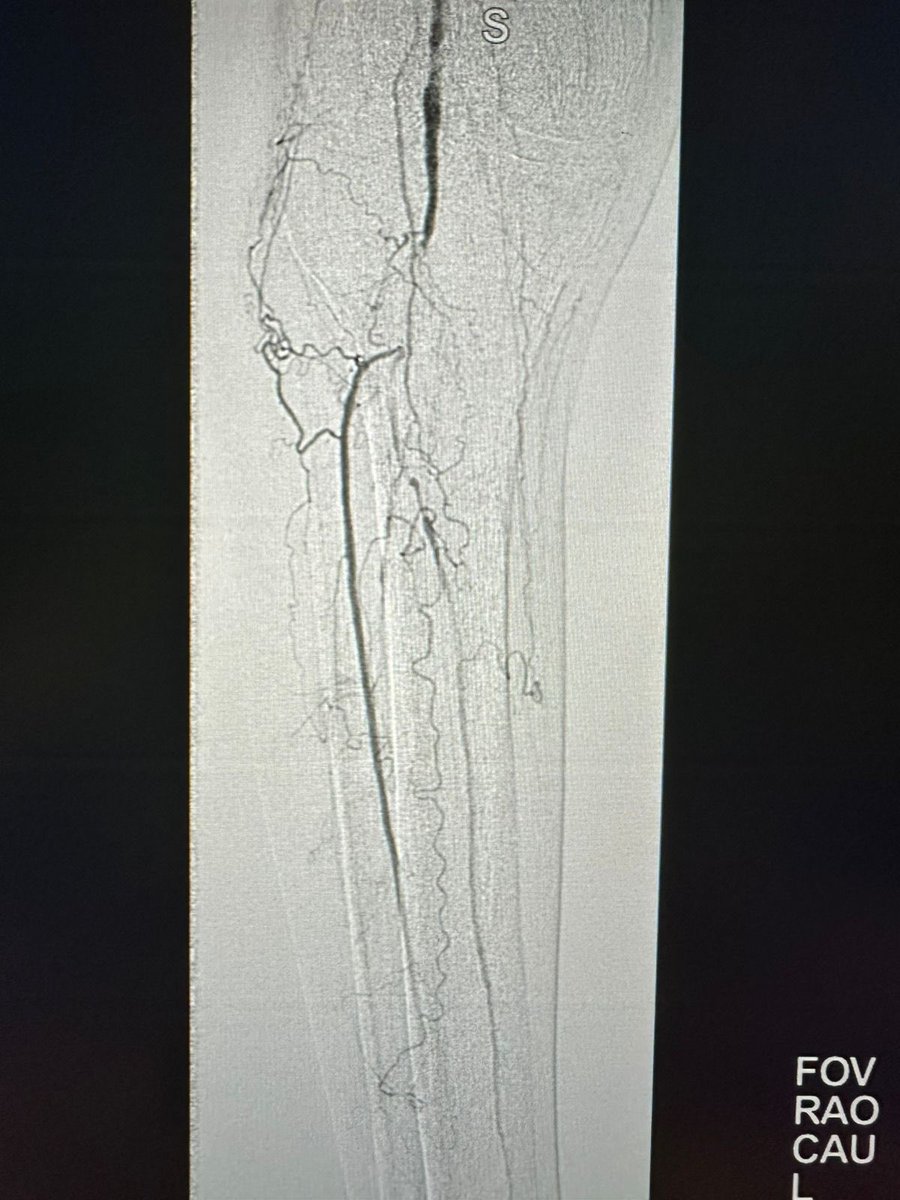

حالة من حالات نقص التروية الدموية الحاد مع وجود جرح غير ملتئم في القدم تم علاجها في وحدة #الأشعة_التداخلية بجامعة الملك سعود بالدخول من شرايين الفخذ والكاحل و إعادة فتح و توسيع الشرايين @ksumedicalcity @_KSU

د.سلطان رباح الحربي | Dr. Sultan R.Alharbi tweet mediaد.سلطان رباح الحربي | Dr. Sultan R.Alharbi tweet mediaد.سلطان رباح الحربي | Dr. Sultan R.Alharbi tweet mediaد.سلطان رباح الحربي | Dr. Sultan R.Alharbi tweet media

في وحدة #الأشعة_التداخلية بجامعة الملك سعود نقوم بتوفير أحدث التقنيات لعلاج القدم السكرية ونقص التروية. الدخول للشرايين يتم من الفخذ ، أو في بعض الحالات المتقدمة من الكاحل أو حتى من اخر القدم. بعض التقنيات لا توجد الا في أماكن قليلة جداً بالشرق الأوسط @ksumedicalcity @_KSU @ksu_medicine @FcmKsu